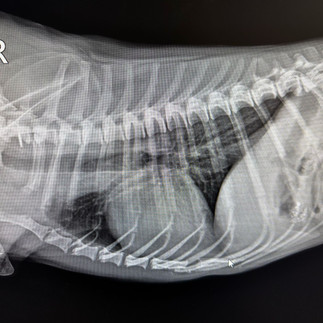

Siamo lieti di presentare alla nostra clientela la nuova Radiologia Digitale Diretta ad alta definizione, in grado di offrire ai nostri pazienti una diagnostica per immagini ancora più affidabile e sicura, soluzione che bypassa le limitazioni delle tecnologie precedenti. La nuova radiologia digitale rappresenta un avanzamento significativo rispetto al passato consentendo una diagnosi più rapida e precisa.

Le immagini vengono acquisite, visualizzate e archiviate in formato elettronico in modo da permettere una gestione più efficiente dei dati migliorando così la cura dei nostri animali.